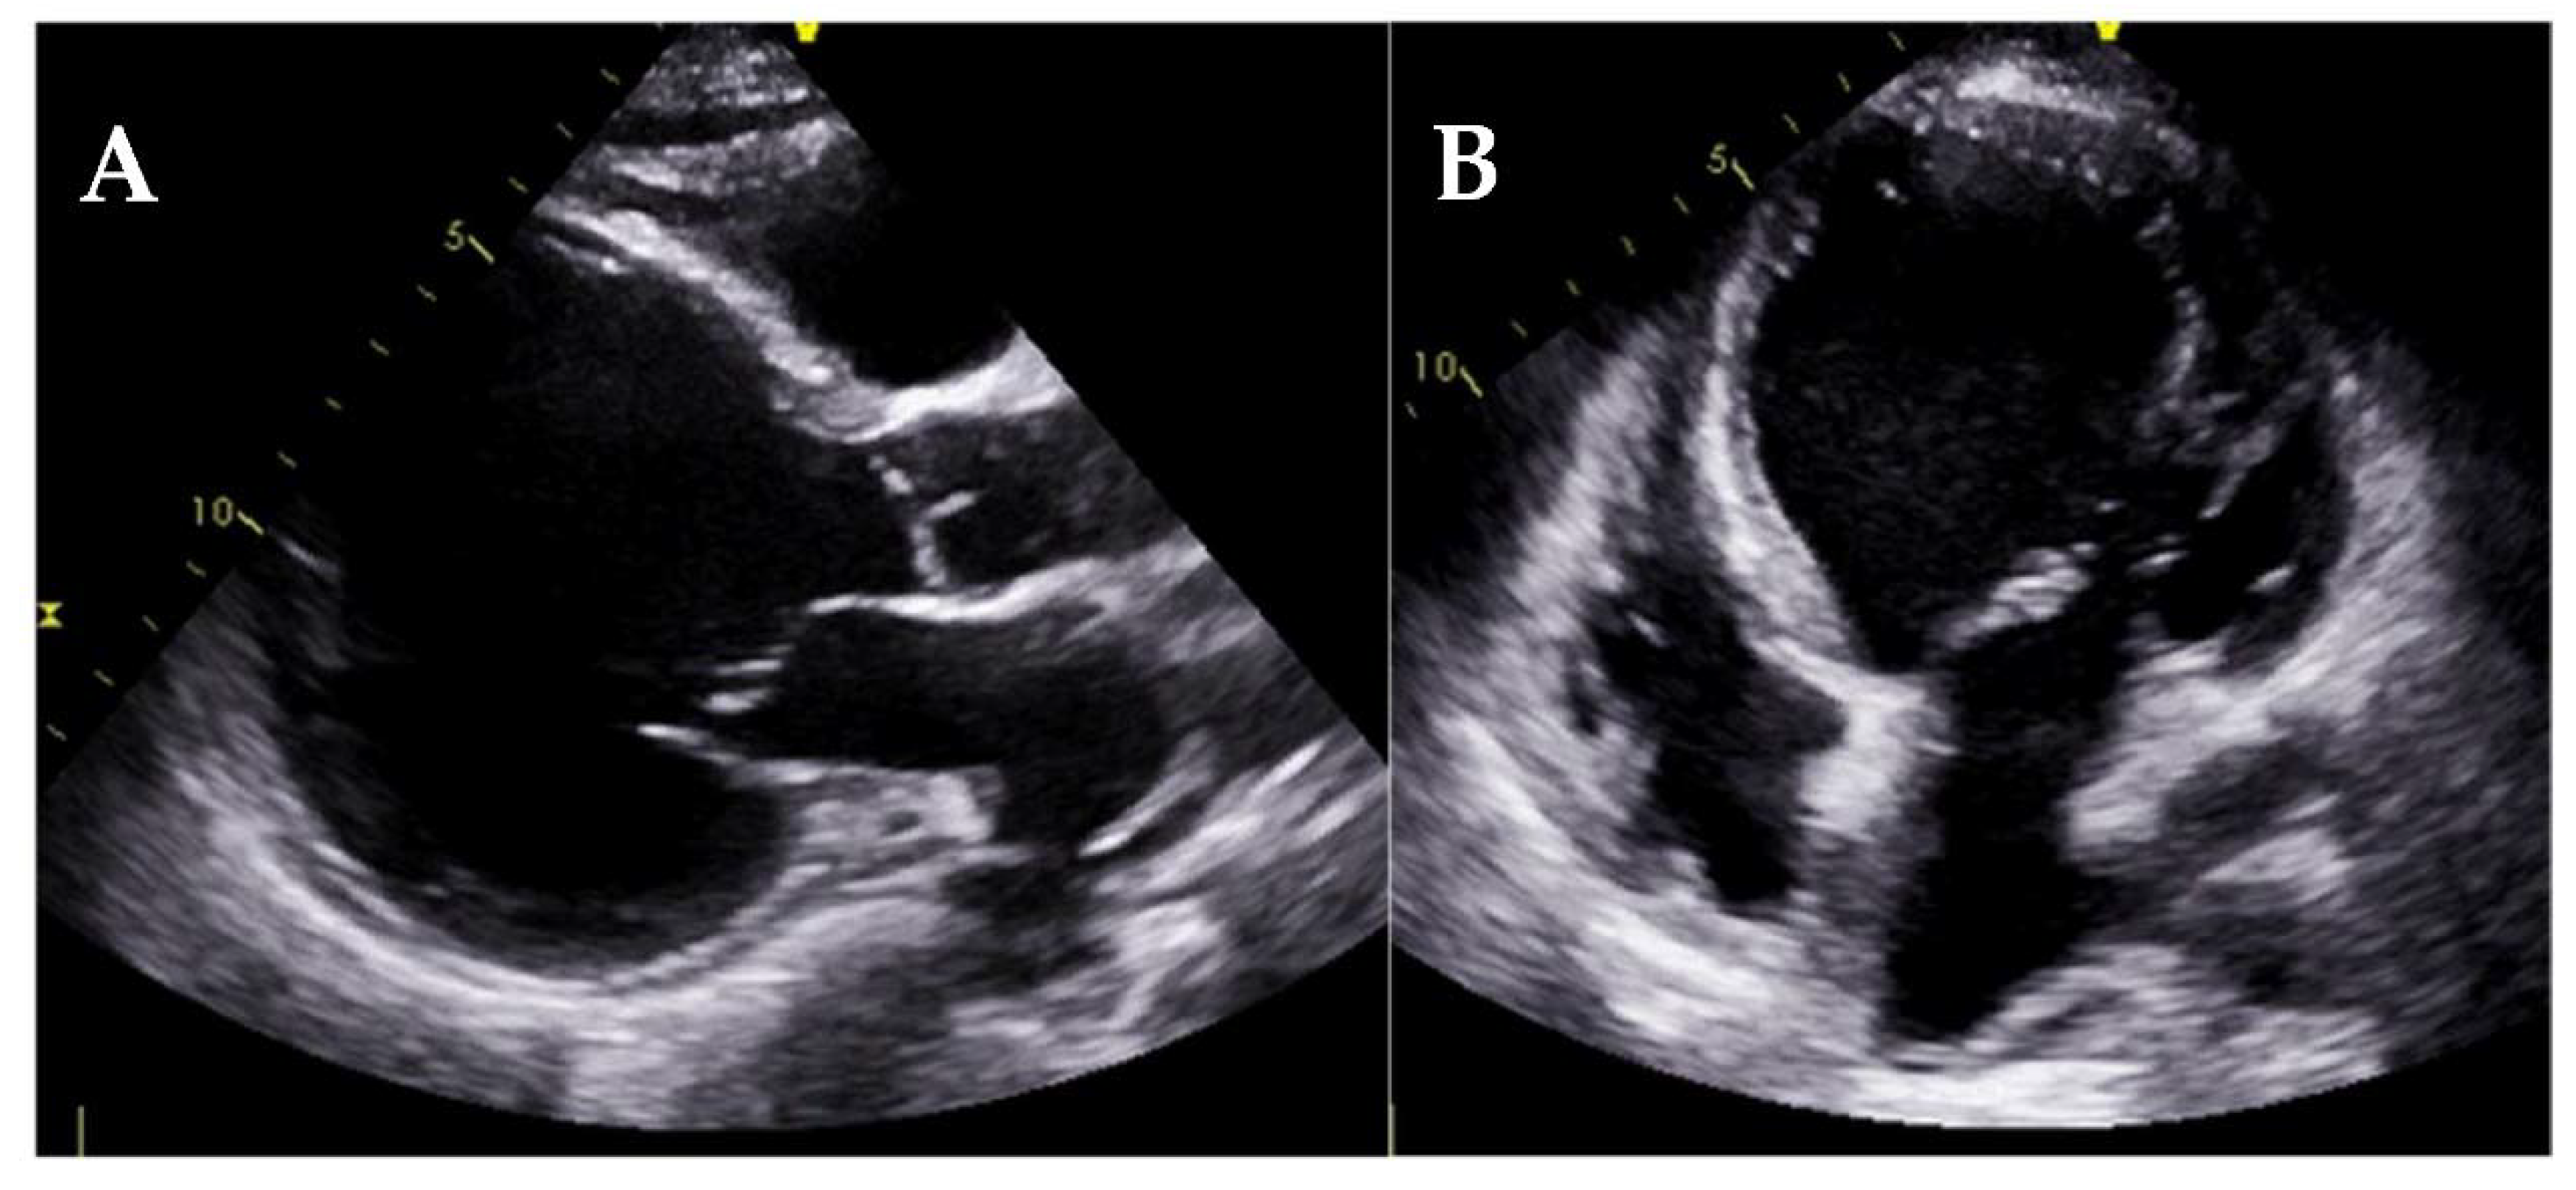

4.6. Endomyocardial Fibrosis